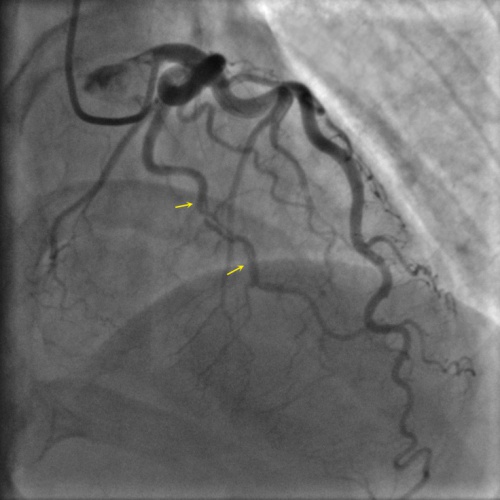

Type 2A

Projection angle: 5 LAO, 34 CRA. Type 2A SCAD is seen in L3.